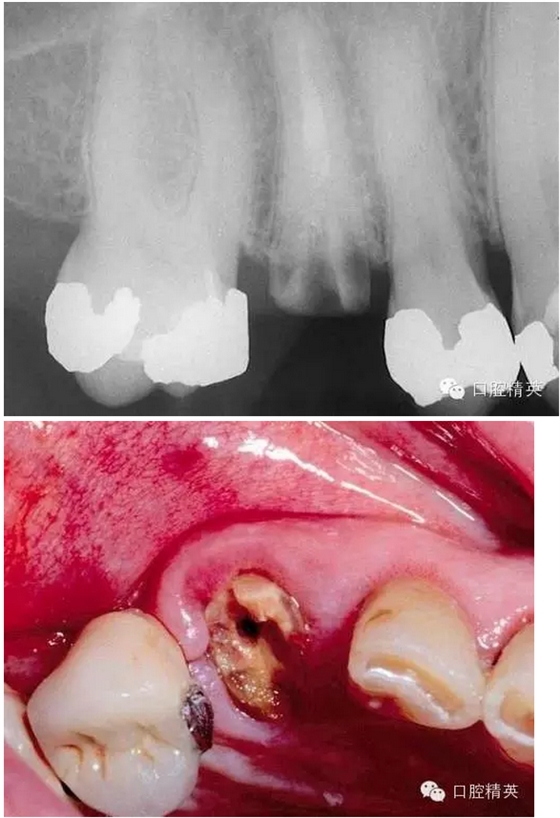

看看一個雙尖牙根的拔除 ,我常常對年輕的大夫說,我覺得難拔的不是下頜阻生智齒,而是有雙根的上頜雙尖牙,特別是一些正畸需要拔出的健康牙。